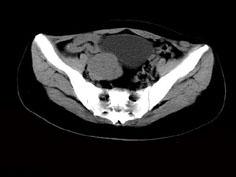

问题 女,24岁,近月余感尿频明显,CT检查如图,最可能诊断为 ( )

选项 A、盆腔纤维瘤 B、卵巢囊肿 C、子宫肌瘤 D、卵巢癌 E、膀胱癌

答案 A